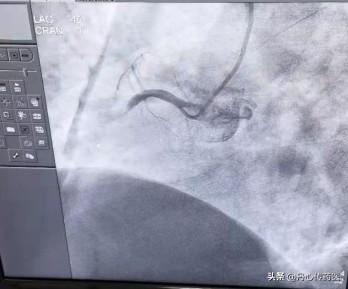

では、この冠動脈はどうかというと、まず写真を見ていただきたい。

矢印は冠動脈を指し、彼の役割は心臓に血液を供給することである。もっとわかりやすく例えるなら、私たちの心臓は一区画の土地で、冠動脈は運河、心筋は作物を育てるためのものだ。もし、運河が塞がれたら。作物は枯れてしまう。この作物が死んでしまうのが心筋壊死です。心筋は血液のポンプであり、もし心筋が強くないなら、私たちの体は十分な栄養を得ることができません。そのため、冠動脈が閉塞すると、心筋は死んでしまいます。これが心筋梗塞である。